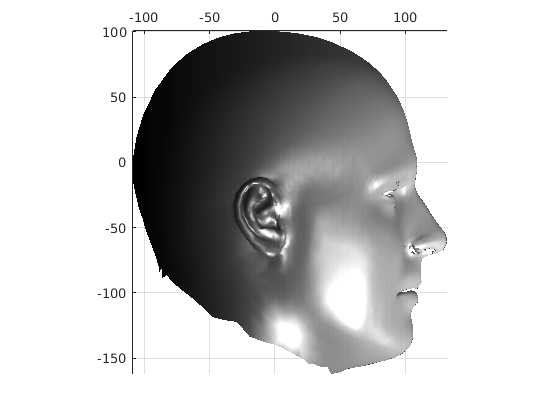

Fig. 9 shows examples of the fitted model (trained on FRGC data) on the first four subjects in our Headspace training set. Note that the mean of the landmarks in the sparse model is centred on the orgin, and so the scan data is moved towards that and becomes frontal in pose. We note that other researchers [28] have used 3D landmark localisation to find the head, but often this only includes landmarks that are relatively easy to localise, namely inner eye corners and nose. Localising more landmarks over a wider facial area has a number of advantage in terms of cropping, pose normalisation and global 3D template warping, all of which are described later.

Following this, OSNR ICP iterates over a set of decreasing mesh stiffnesses (typically 10), until the registration between the template and the scan is below some error or a maximum number of iterations is reached. Figure 28 shows a selection of template warp results. The template appears to be accurately warped onto the scan, at least in the normal direction of the surfaces, it is not possible to see error tangential to the surface. Furthermore, we have noted errors on some scans on the ears. To improve these we need a method of automatically landmarking the ears, which is an area for further work.

The first two modes of head variation are shown in figures 29 and 30. These include the cranial height / facial angle mode and the (almost) pure size mode, as seen in the sagittal profile model.